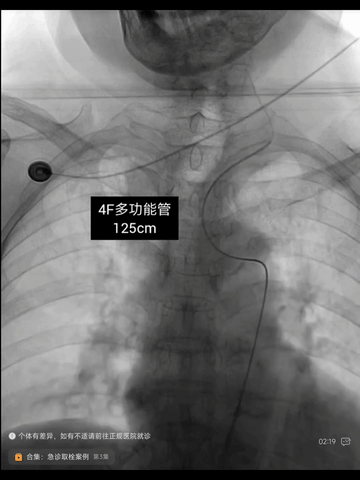

4F多功能管(125cm)+6F长鞘(90cm Cook)同轴,长鞘送至左CCA远端,泥鳅导丝导引中间管(6F,115cm)至左ICA海绵窦段,并长鞘推送到C1远段。